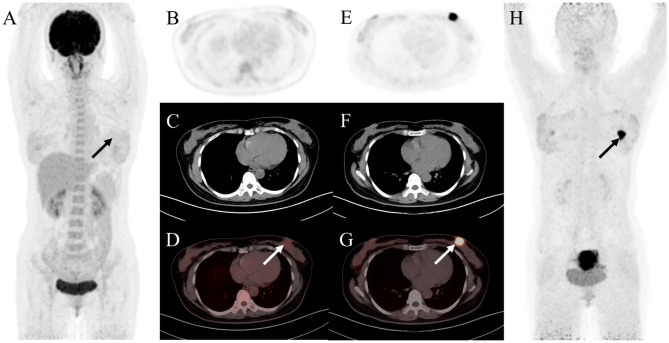

{"title":"Head-to-head comparison of <sup>18</sup>F-FDG and <sup>68</sup>Ga-FAPI PET/CT in common gynecological malignancies.","authors":"Tengfei Li, Jintao Zhang, Yuanzhuo Yan, Yue Zhang, Wenjie Pei, Qingchu Hua, Yue Chen","doi":"10.1186/s40644-025-00843-7","DOIUrl":null,"url":null,"abstract":"<p><strong>Background: </strong><sup>68</sup>Ga-FAPI (fibroblast activation protein inhibitor) is a novel and highly promising radiotracer for PET/CT imaging. It has shown significant tumor uptake and high sensitivity in lesion detection across a range of cancer types. We aimed to compare the diagnostic value of <sup>68</sup>Ga-FAPI and <sup>18</sup>F-FDG PET/CT in common gynecological malignancies.</p><p><strong>Methods: </strong>This retrospective study included 35 patients diagnosed with common gynecological tumors, including breast cancer, ovarian cancer, and cervical cancer. Among the 35 patients, 27 underwent PET/CT for the initial assessment of tumors, while 8 were assessed for recurrence detection. The median and range of tumor size and maximum standardized uptake values (SUV<sub>max</sub>) were calculated.</p><p><strong>Results: </strong>Thirty-five patients (median age, 57 years [interquartile range], 51-65 years) were evaluated. In treatment-naive patients (n = 27), <sup>68</sup>Ga-FAPI PET/CT led to upstaging of the clinical TNM stage in five (19%) patients compared with <sup>18</sup>F-FDG PET/CT. No significant difference in tracer uptake was observed between <sup>18</sup>F-FDG and <sup>68</sup>Ga-FAPI for primary lesions: breast cancer (7.2 vs. 4.9, P = 0.086), ovarian cancer (16.3 vs. 15.7, P = 0.345), and cervical cancer (18.3 vs. 17.1, P = 0.703). For involved lymph nodes, <sup>68</sup>Ga-FAPI PET/CT demonstrated a higher SUV<sub>max</sub> for breast cancer (9.9 vs. 6.1, P = 0.007) and cervical cancer (6.3 vs. 4.8, P = 0.048), while no significant difference was noted for ovarian cancer (7.0 vs. 5.9, P = 0.179). Furthermore, <sup>68</sup>Ga-FAPI PET/CT demonstrated higher specificity and accuracy compared to <sup>18</sup>F-FDG PET/CT for detecting metastatic lymph nodes (100% vs. 66%, P < 0.001; 94% vs. 80%, P < 0.001). In contrast, sensitivity did not differ significantly (97% vs. 86%, P = 0.125). For most distant metastases, <sup>68</sup>Ga-FAPI exhibited a higher SUV<sub>max</sub> than <sup>18</sup>F-FDG in bone metastases (12.9 vs. 4.9, P = 0.036).</p><p><strong>Conclusions: </strong><sup>68</sup>Ga-FAPI PET/CT demonstrated higher tracer uptake and was superior to <sup>18</sup>F-FDG PET/CT in detecting primary and metastatic lesions in patients with common gynecological malignancies.</p><p><strong>Trial registration: </strong>ChiCTR, ChiCTR2100044131. Registered 10 October 2022, https://www.chictr.org.cn , ChiCTR2100044131.</p>","PeriodicalId":9548,"journal":{"name":"Cancer Imaging","volume":"25 1","pages":"21"},"PeriodicalIF":3.5000,"publicationDate":"2025-02-28","publicationTypes":"Journal Article","fieldsOfStudy":null,"isOpenAccess":false,"openAccessPdf":"https://www.ncbi.nlm.nih.gov/pmc/articles/PMC11869701/pdf/","citationCount":"0","resultStr":null,"platform":"Semanticscholar","paperid":null,"PeriodicalName":"Cancer Imaging","FirstCategoryId":"3","ListUrlMain":"https://doi.org/10.1186/s40644-025-00843-7","RegionNum":2,"RegionCategory":"医学","ArticlePicture":[],"TitleCN":null,"AbstractTextCN":null,"PMCID":null,"EPubDate":"","PubModel":"","JCR":"Q2","JCRName":"ONCOLOGY","Score":null,"Total":0}

Results: Thirty-five patients (median age, 57 years [interquartile range], 51-65 years) were evaluated. In treatment-naive patients (n = 27), 68Ga-FAPI PET/CT led to upstaging of the clinical TNM stage in five (19%) patients compared with 18F-FDG PET/CT. No significant difference in tracer uptake was observed between 18F-FDG and 68Ga-FAPI for primary lesions: breast cancer (7.2 vs. 4.9, P = 0.086), ovarian cancer (16.3 vs. 15.7, P = 0.345), and cervical cancer (18.3 vs. 17.1, P = 0.703). For involved lymph nodes, 68Ga-FAPI PET/CT demonstrated a higher SUVmax for breast cancer (9.9 vs. 6.1, P = 0.007) and cervical cancer (6.3 vs. 4.8, P = 0.048), while no significant difference was noted for ovarian cancer (7.0 vs. 5.9, P = 0.179). Furthermore, 68Ga-FAPI PET/CT demonstrated higher specificity and accuracy compared to 18F-FDG PET/CT for detecting metastatic lymph nodes (100% vs. 66%, P < 0.001; 94% vs. 80%, P < 0.001). In contrast, sensitivity did not differ significantly (97% vs. 86%, P = 0.125). For most distant metastases, 68Ga-FAPI exhibited a higher SUVmax than 18F-FDG in bone metastases (12.9 vs. 4.9, P = 0.036).